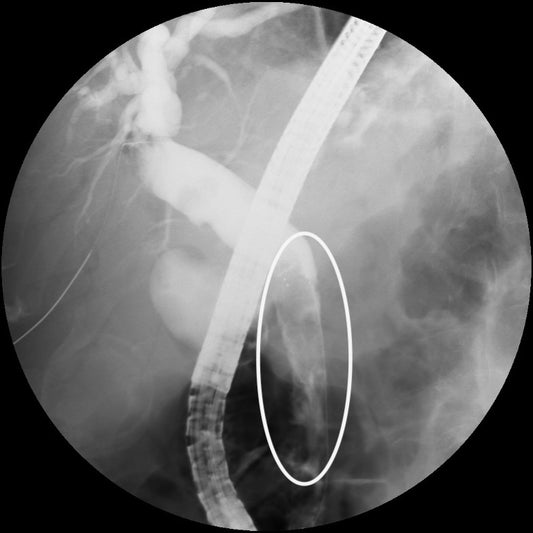

Abdominal Pain, Jaundice and Melena – Think of ...

A 58-year-old patient with NAFLD, diabetes mellitus and hypertension underwent a liver biopsy for a 3 cm nodule in segment VI of the liver. About 24-hours later the patient complained...